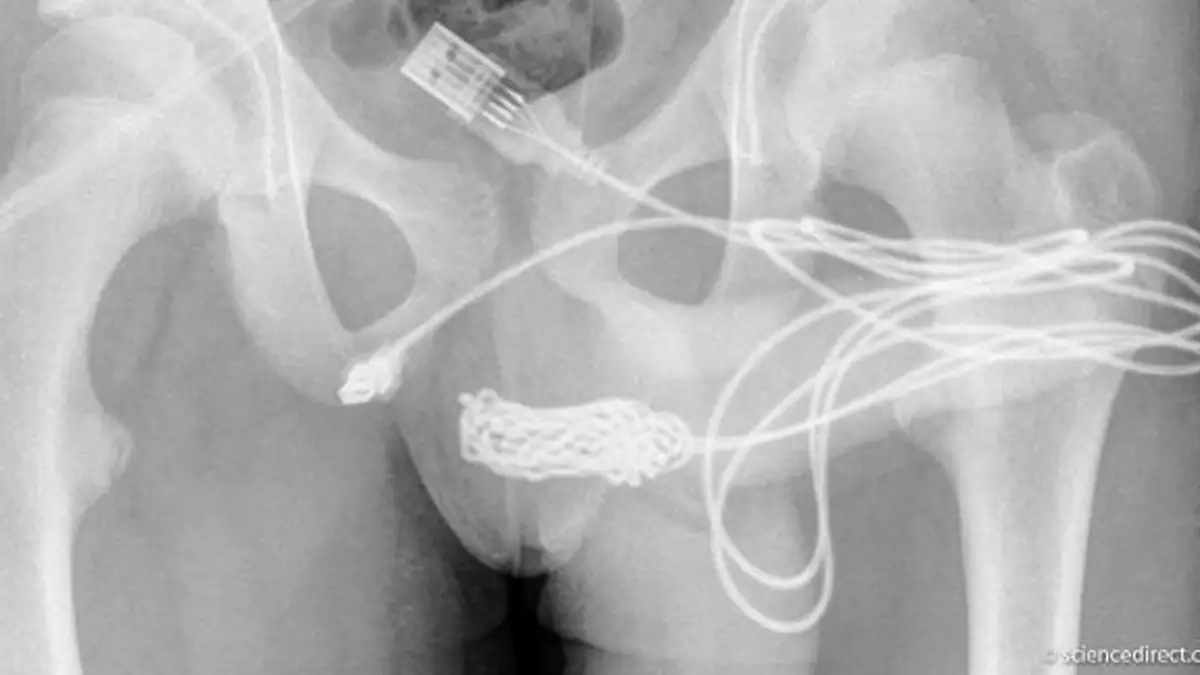

Wie es aus dem Bericht des Fachmagazins „Urology Case Reports“ hervorgeht, soll das besagte Kabel zu allem Übel auch noch verknotet gewesen sein. Es war dem 15-Jährige unmöglich, das Kabel selbst wieder zu entfernen. Die Situation endete äußerst peinlich, denn der Junge musste sich Hilfe suchen und gemeinsam mit seiner Mutter in ein Krankenhaus fahren.

Doch: „Manuelle und endoskopische Entfernungsversuche waren erfolglos.“ Schließlich musste ein Chirurg ran und eine Not-OP konnte dem 15-Jährigen nicht erspart bleiben. Dieser entfernte das Kabel durch eine sogenannte Harnröhrenschlitzung. Fremdkörper wie diesen einzuführen, ist laut den Spezialisten eine sehr „heikle Angelegenheit“.